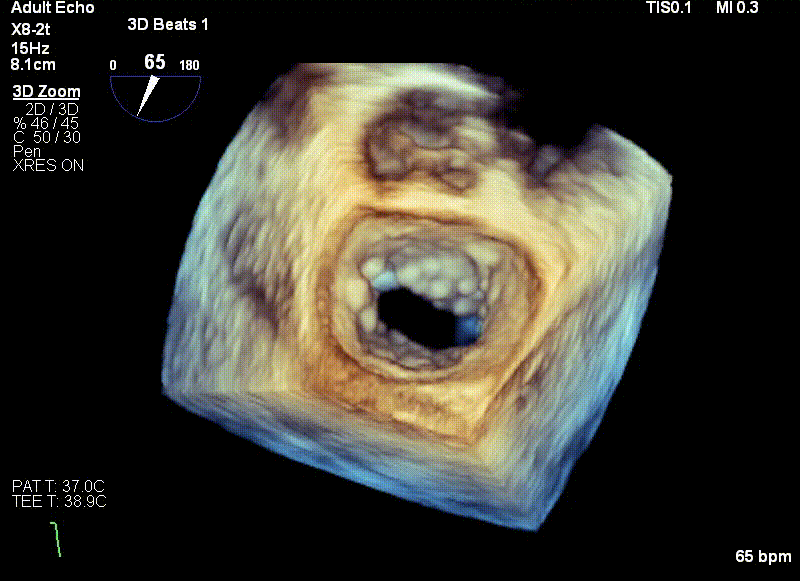

王建安教授调整二尖瓣夹轨迹和方向,使其轨迹垂直于二尖瓣环平面且指向心尖,定位于二尖瓣C1区且指向1-7点钟方位。

经食道超声引导后,王建安教授将二尖瓣夹NTR夹取C1区瓣叶,准确成功捕获C1前叶和后叶反流最严重区域,并予夹合。使二尖瓣在收缩期由大的单孔变成一大一小的双孔,显著减少了二尖瓣反流。